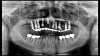

(14. and 15.) Photograph of fractured right lateral incisor taken with a smartphone and an EALS device during patient presentation for emergency treatment shown with accompanying radiograph.

(16. and 17.) Photograph of failing implant prosthetics that may require specialty care taken with a smartphone and an EALS device.

Emergency visits are a common and unpredictable occurrence at nearly all dental practices (Figure 14 and Figure 15). When an emergency occurs, the patient's provider may not always be available to evaluate and initiate treatment. In a similar manner, new patients of record frequently present with oral conditions that require the attention of a dental specialist who may only be available at another clinic (Figure 16 and Figure 17). For many of these patients, immediate access to care may be limited, and if a patient is experiencing discomfort, time will be a critical factor in regard to initiating a proposed plan of action. The use of a smartphone with an EALS can allow the clinical staff to rapidly acquire intraoral photographs or a video and transmit these images and other information via encrypted text message or secure e-mail to anywhere in the world for immediate consultation. The combination of telecommunications and dentistry is known as teledentistry,13 which has been shown to impart significant benefits to patients and providers in the fields of oral medicine,14 oral and maxillofacial surgery,15 endodontics,16 prosthodontics,17 periodontics,18 pediatrics,19 orthodontics,20 and oral hygiene.21